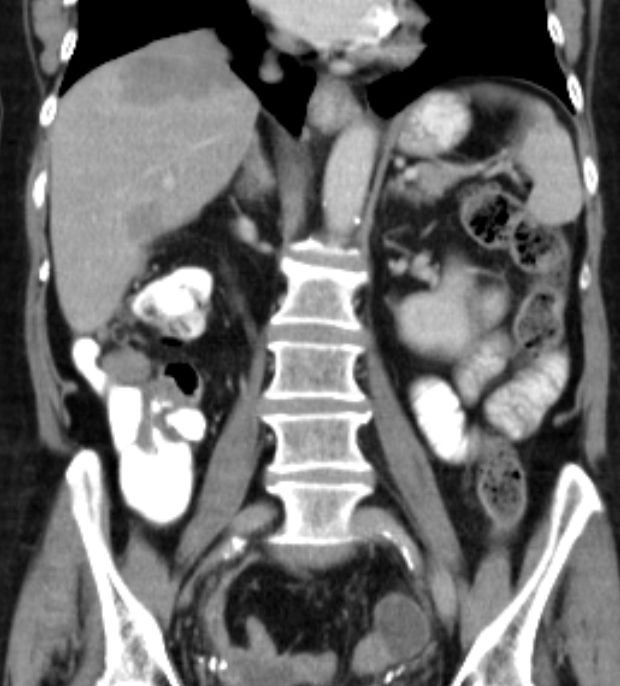

76-jährige Frau, die vor 13 Jahren ein Ovarial-Karzinom pT3b pNo Mo Lo Vo G2 hatte. Radikale OP, 6x Taxol - Carboplatin. Jetzt Lebermetastasen, RF linker Adnexbereich.